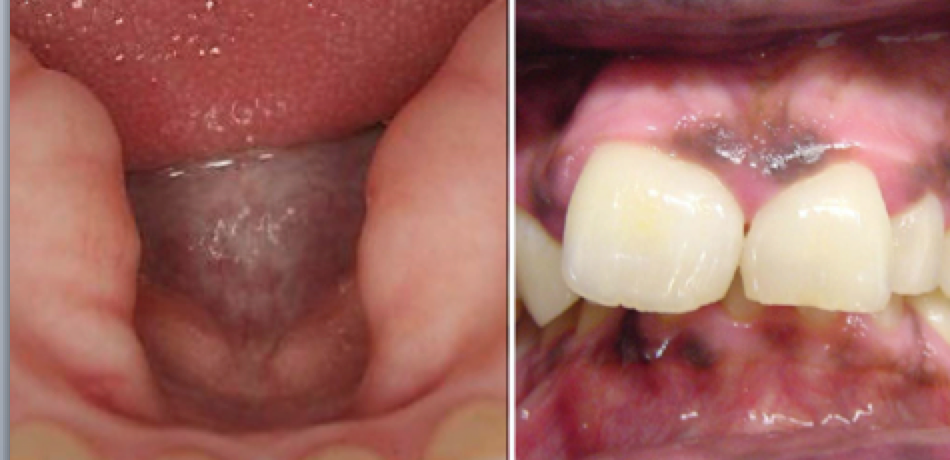

macule: flat change in color

patch: flat change in color >1 cm

plaque: solid, raised, flat topped lesion

pseudomembrane: removable plaque

erosion- depressed lesion w/ partial loss of epithelium

ulcer- depressed lesion w/ total loss of epithelium